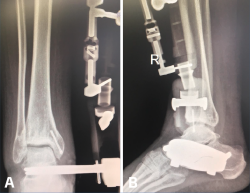

Utilizamos el fijador articulado monolateral (de tipo X-Caliber®, Orthofix). En un primer paso procedemos a colocar los pines en astrágalo y calcáneo mediante la guía radiotransparente (Figura 2), para posteriormente colocar los pines tibiales en la superficie anteromedial de la misma (a ser posible 3). Al acabar el procedimiento procedemos a realizar progresivamente una distracción de entre 7 y 8 mm (se dispone de un calibrador en el fijador que nos permite visualizar la distracción que estamos realizando) (Figura 3) bajo control radioscópico, dejando finalmente la pieza articulada totalmente libre para la movilidad tibioastragalina desde el principio. Aplicamos un vendaje compresivo de la extremidad y retiramos la isquemia (Figuras 4 y 5).

Figura 4. A y B: radiografías anteroposterior y lateral del fijador implantado con la distracción conseguida a nivel articular.

Figura 7. Caso de la Figura 6 con distracción articulada.